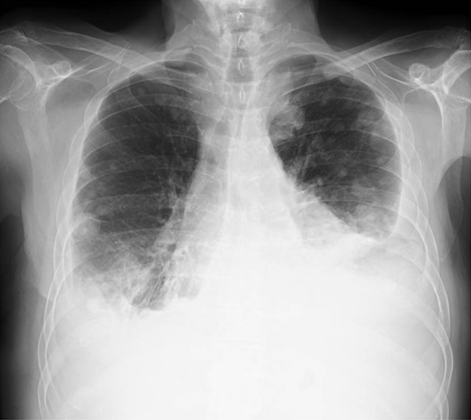

We report a case of a 64-year-old non-smoking male, who had had intermittent exposure to asbestos for three years. He had been undergoing treatment for hypertension. He presented with dyspnea on moderate exertion that had developed over several days, discomfort in the left hemithorax, and some intolerance to decubitus positions. The patient had a weight loss 10 kg in the last three months. A physical examination showed that he was conscious and lucid with normal coloring. Respiratory auscultation revealed hypophonesis in the lower half of the left hemithorax and right basal hemithorax. Hematological and hepatic findings were within the normal range. Tumor markers carbohydrate antigen (CA) 125, carcinoembryonic antigen (CEA), alpha-fetoprotein (AFP), CA 15-3, and CA 19-9 were shown to be within the normal range. Simple radiography of the posterior-anterior thorax showed bilateral pleural effusion with multiple nodular images in both hemithoraces (Figure 1). A contrast computed tomography (CT) scan of the thorax and abdomen revealed multiple bilateral pulmonary and pleural lesions, mediastinal lymphadenopathies (Figure 2), intra-abdominal implants (Figure 3), and a 56×40 mm polylobulated mass in the left buttock (Figure 4). A biopsy of the mass in the left buttock was made with an 18-gauge needle. Pathological study involved obtaining three cores of tissue measuring between 0.7 and 1 cm in length that were fixed in formalin. In the histological sections, we observed connective tissue infiltrated by epithelioid cells arranged in nests and trabeculae that showed atypia with hyperchromatic nuclei and prominent nucleoli. Occasional non-atypical mitosis was also detected (Figure 5). Immunohistochemical study revealed cytoplasmic positivity for keratins 5/6 and 7. Nuclear and cytoplasmic positivity was observed for calretinin, while nuclear positivity was detected for Wilms tumor 1 protein (Figure 6). Negative results were found for epithelial membrane antigen (Ber-Ep4), thyroid transcription factor-1 (TTF-1), protein suppressor p63, keratin 20, CEA, prostate-specific antigen (PSA), renal cell carcinoma (RCC), vimentin, common lymphoblastic leukemia antigen (CD10), S-100 protein, and CA 19.9. These results confirmed the diagnosis of metastasis of epithelioid mesothelioma. The patient passed away eight days later.

Figure 1: Simple radiography of the posterior-anterior thorax. Mediastinal widening with abundant bilateral pleural effusion, predominantly on the left side and the presence of multiple bilateral pulmonary nodules.